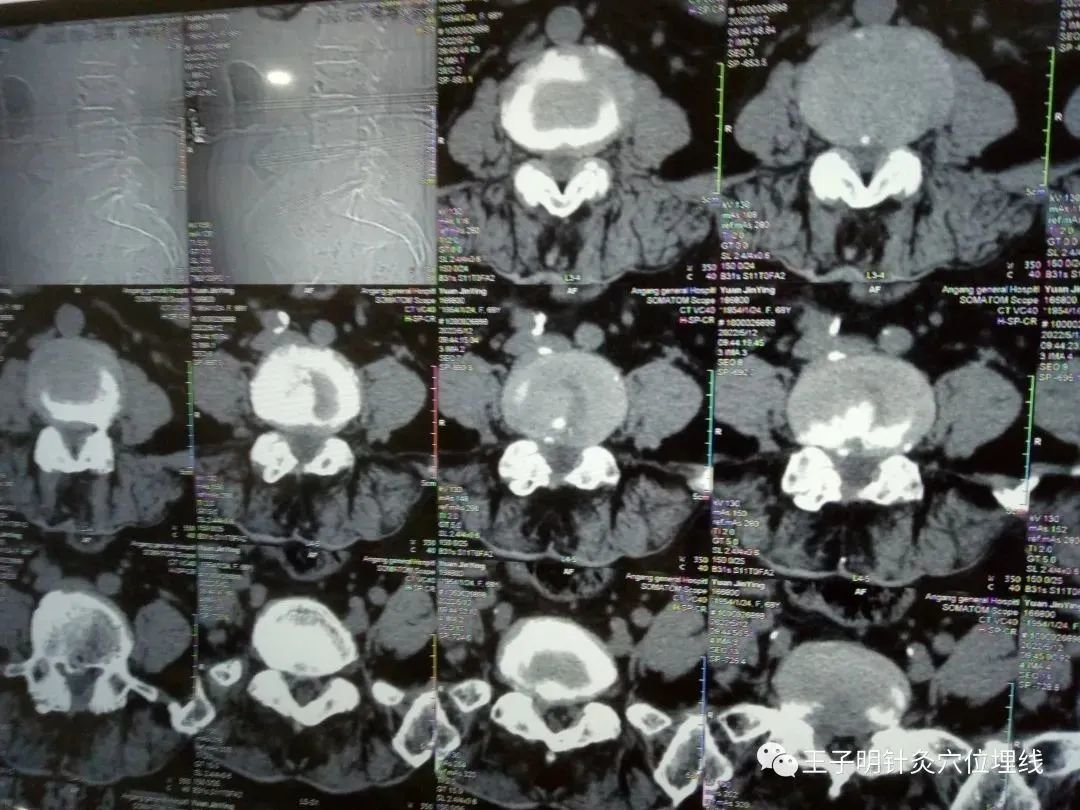

患者自述 : 三年前患病,腰椎间盘突出压迫神经根引起的腰腿疼痛,在医院做了腰椎间盘突出手术摘除,手术后一年左右感觉可以,等一年过后疼痛又开始加重,经多家医院多种方法治疗不见好转,经朋友介绍过来治疗,见腰椎CT片所示 :

见腰椎间盘手术后,L3.4脊突、L4.5脊突、L5骶一脊突缺损严重(手术切掉的脊突),又见腰椎间盘突出,椎管狭窄,腰椎手术过后手术刀口线达到16公分余,一年多时间里,腰腿疼痛严重,生活不能自理,多种方法治疗效果一般,每天只能靠吃止痛药缓解疼痛,因为吃药物太多,胃肠不舒,饮食减少,面容憔悴。